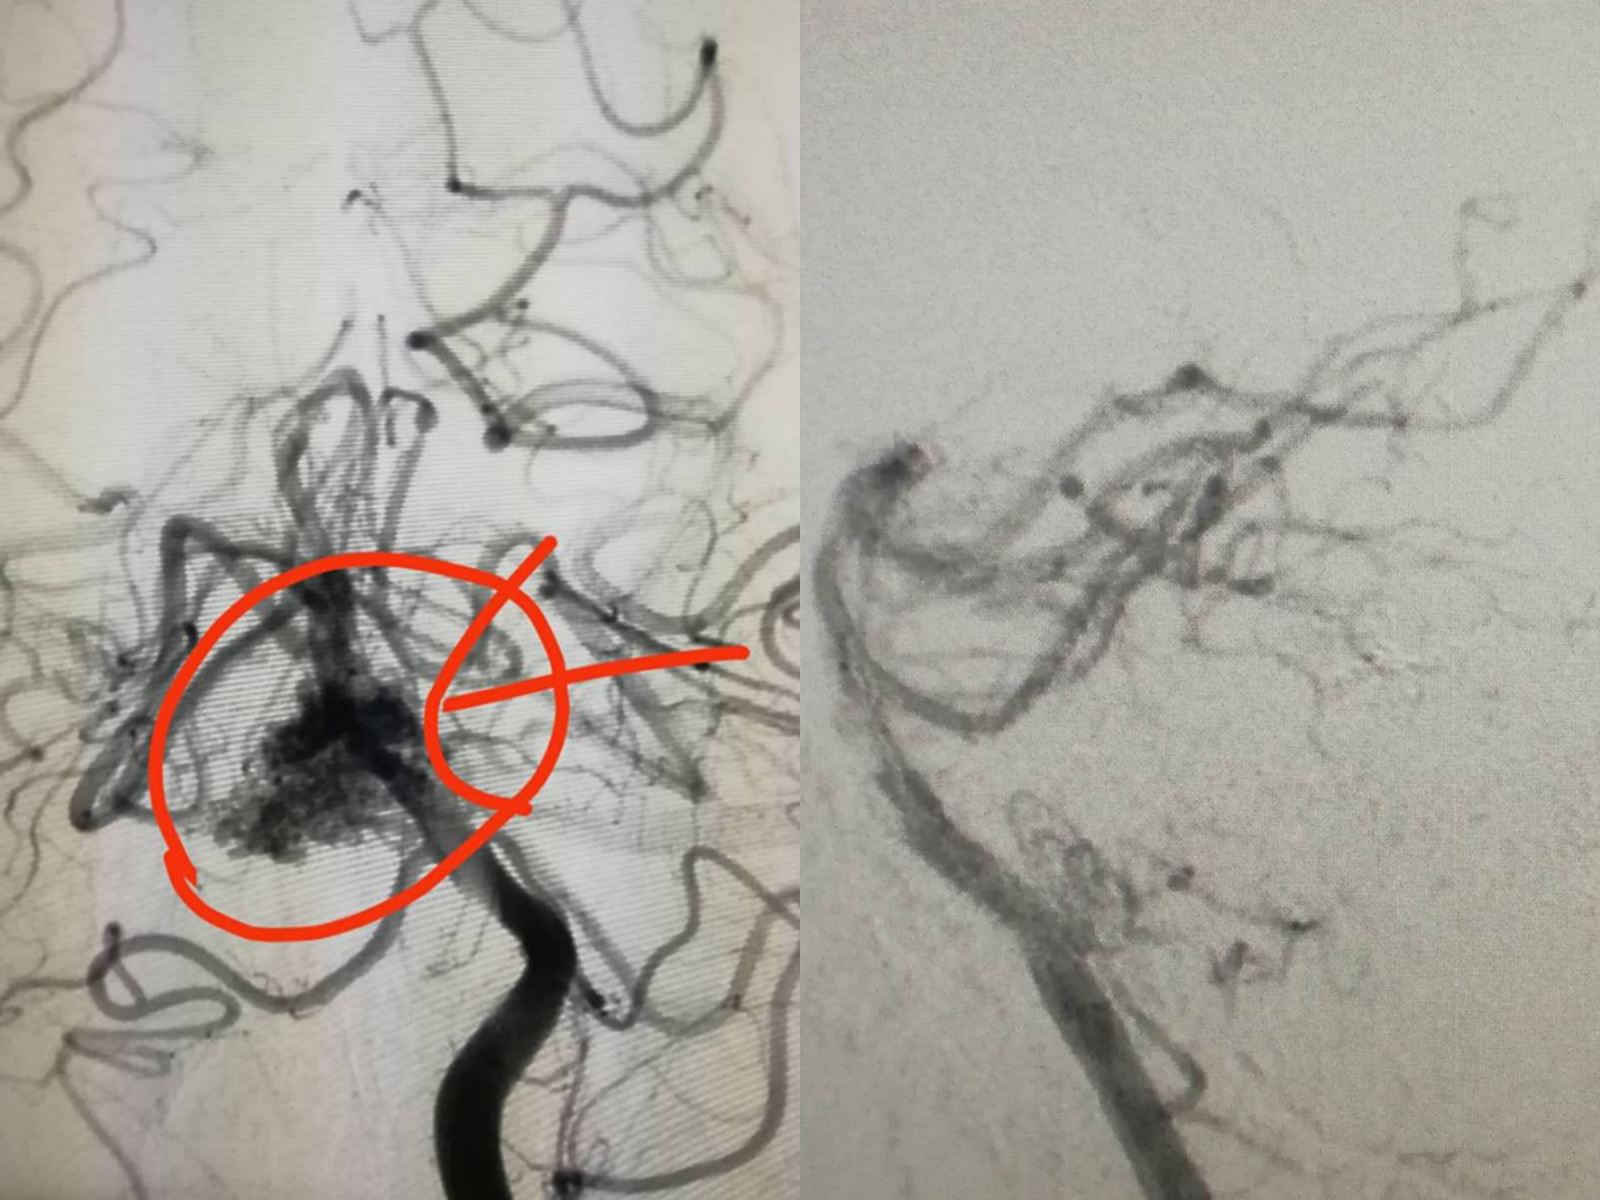

患者宋某,男性,26岁,因突发头痛、头晕、恶心、呕吐等症状来我院就诊,经CT检查提示:右侧小脑出血,患者既往无高血压病史,首诊医生张永哲主任医师考虑出血原因可能为脑血管畸形,经进一步造影检查证实:右侧小脑动静脉畸形(AVM)。患者家属一方面担心患者病情发展恶化,另一方面家庭经济存在困难,并且在新冠肺炎疫情的特殊阶段不具备转院条件,经家属多次请求,科内组织多次讨论,神经外科团队决定为患者行介入栓塞术治疗。4月5日,在刘光宇主任指导下,由张永哲医生主刀、赵程欣医生和李兵桥医生担任助手组成的医疗团队,在麻醉师高飞和导管室护理团队的积极配合下,成功为患者实施介入脑动静脉畸形栓塞术。术中,张永哲医生凭借精湛的医技和多年的神经外科临床经验,利用微导管反复超选,准确找到供血动脉,将微导管精准到位后,利用出色的手感成功注入ONYX胶0.4ml,完美栓塞畸形团块且无动脉端反流和静脉端跑胶现象。该手术仅用1小时成功完成,术后给予患者相关后续治疗,目前患者恢复情况较好,术前症状全部消失,可自行下地活动,未留下任何后遗症。

脑动静脉畸形(arteriovenous malformation,AVM)是一种先天性局部脑血管发生的变异。在病变部位脑动脉和脑静脉之间缺乏毛细血管,致使动脉与静脉直接相通,形成动静脉之间的短路,导致一系列脑血流动力学的紊乱的症状。临床上常表现为反复的颅内出血、部分性或全身性癫痫发作、短暂性脑缺血发作和进行性神经功能障碍。一旦发生出血,死亡率极高,以前类似病例一般都转院治疗。据悉,自治区仅有两家医院能够完成此项手术。